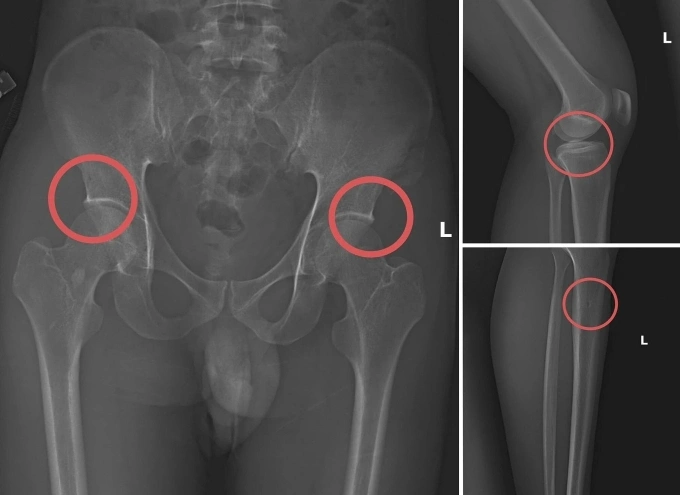

Cách cán bộ y tế dùng búa đinh đục gãy xương chân để trục lợi bảo hiểm

Phú Thọ- Tạ Minh Châu, nguyên cán bộ y tế, đã cho người mua bảo hiểm nhân thọ giá trị cao, rồi tiêm thuốc mê, dùng búa đinh đục gãy xương chậu, đùi của họ để cùng trục lợi tiền.